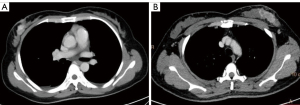

Images were transmitted to the Philips post-processing workstation [IntelliSpace Portal (ISP) version 9.0, Philips Healthcare] after scanning. All images were reconstructed using a conventional iDose reconstruction algorithm and spectral reconstruction in projection space, resulting in conventional mixed energy images (CIs) and spectral-based images (SBIs). Two sets of VNC images: arterial-phase VNC (VNC-A) images and venous-phase VNC (VNC-V) images were reconstructed based on arterial and venous SBIs for comparative analysis. The reconstructed layer thickness and interlayer spacing of all images were 1 mm. Images were analyzed using the ISP workstation, and the three-phase images were reviewed at consistent levels, including plain scan, arterial phase, and venous phase (Figure 1).

Subjective evaluation: two radiologists with 5 years of experience in breast imaging diagnosis evaluated the images and conducted a consistency analysis of the evaluation results. The evaluation criteria were as follows: excellent (5 points): the absence of artifacts or noise in the image allows for clear visualization of the anatomical structures of the breast and surrounding tissues in the chest, thereby meeting diagnostic standards. Good (4 points): the presence of some artifacts and noise slightly diminishes image quality but still displays glands and blood vessels in the breast. Poor (3 points): images with severe artifacts and noise significantly impede the visualization of anatomical details in the breast, rendering them inadequate for diagnostic purposes (Figure 2).